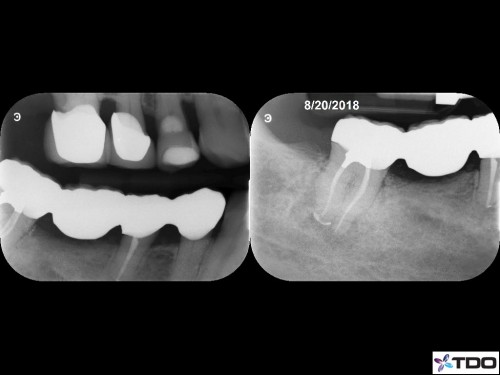

#31 Purulent drainage 3v 1

66 yof

ER patient. Left drainage hole and medicated/closed 3 days later.

Asymptomatic at the complete appt 20 days later.